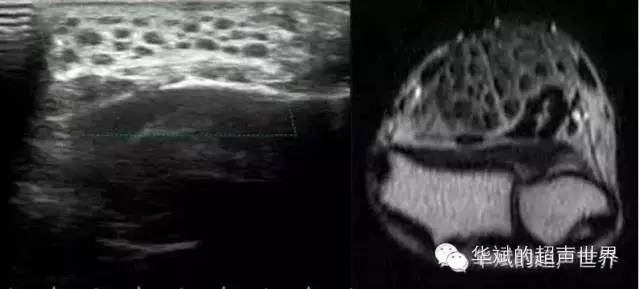

也称纤维脂瘤性错构瘤、脂肪纤维瘤性错构瘤,是一种少见病变,病因是纤维脂肪组织对大神经及其分支的逐渐渗透。该病手部易患,最常累及正中神经,桡神经和尺神经也可受累。其他的偶尔累及的部位还有腓总神经、坐骨神经和指神经等。尽管这种病变不是恶性的,但临床表现可能很明显。纤维脂肪性错构瘤常见于儿童、青少年或年轻成人,临床可见逐渐增大的肿块、巨指(趾)以及神经压迫症状等等。这类错构瘤可能与脂瘤性营养异常性巨大增生有关。超声显示低回声的声束周围被高回声的纤维脂肪结构包绕,呈现为典型的“蛇纹样”改变。MRI上也可以同时显示纤维组织和脂肪组织的特征,增大的神经呈蛇纹样特征表现。大体检查可见灰色或黄色肿块包绕神经,组织学上见纤维脂肪浸润以及神经鞘膜和神经周围纤维化。

图6纤维脂瘤性错构瘤。19岁男性,腕部肿胀。超声和MRI显示正中神经增粗,神经束周围被纤维脂肪样结构包绕,呈“蛇皮样”表现。